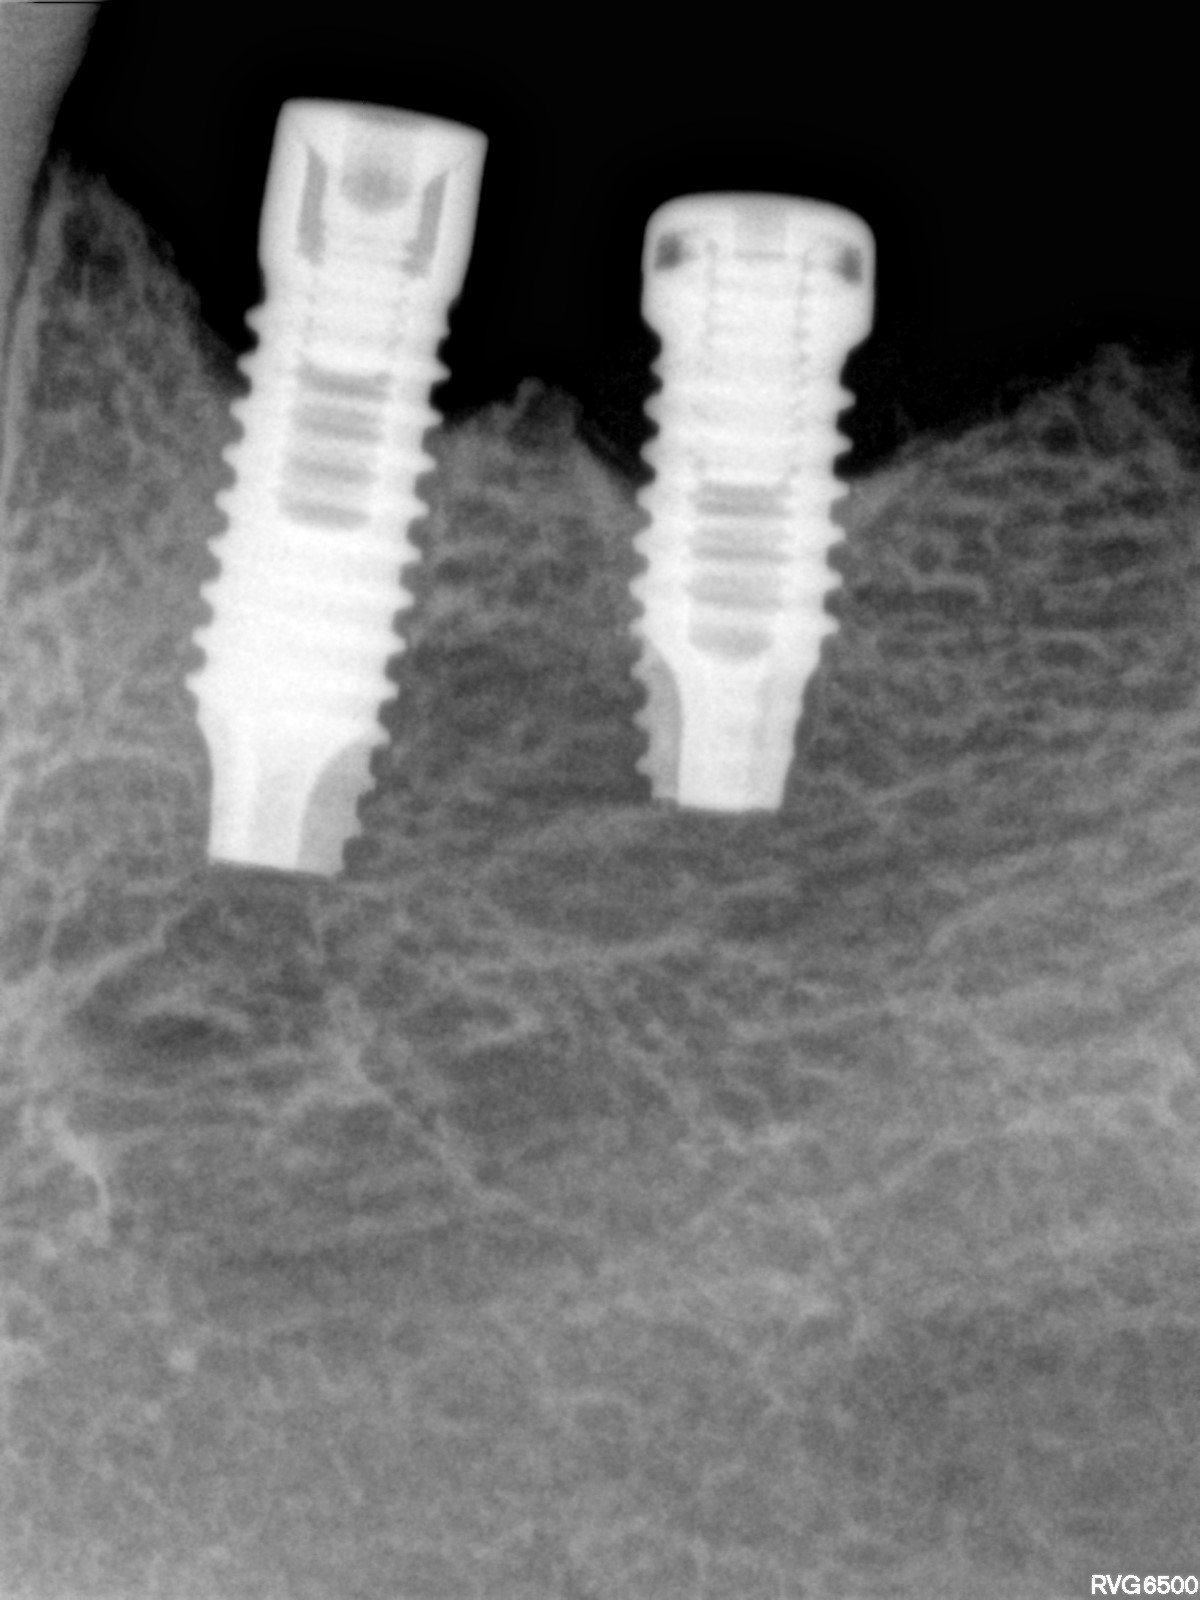

Paciente_Hermina Vintiu

Implantes colocados na Roménia +/- à 5 anos. Saber marca e modelo para poder reabilitar. Obrigada